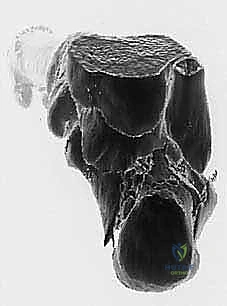

تُظهر الصورة أعلاه فحصاً بالأشعة المقطعية يوضح مدى تعقيد الكسر الأولي والإزاحة التي تحدث، مما يسلط الضوء على التشريح الفوري بعد الإصابة والذي يمهد لسوء الالتئام إذا لم يُعالج بدقة.

3. التصوير المقطعي المحوسب (CT Scan) مع إعادة البناء ثلاثي الأبعاد (3D Reconstruction)

لا يمكن التخطيط لجراحة تصحيح سوء التئام عظم العقب بدون أشعة مقطعية. توفر الأشعة المقطعية رؤية دقيقة للتشريح العظمي المشوه، وتحدد بدقة مكان الانحشار الشظوي، حالة الأسطح المفصلية، ومسار الأوتار. التخطيط ثلاثي الأبعاد يسمح للجراح ببناء نموذج افتراضي للقدم وتحديد أماكن القطع العظمي المطلوبة بدقة مليمترية قبل الدخول إلى غرفة العمليات.